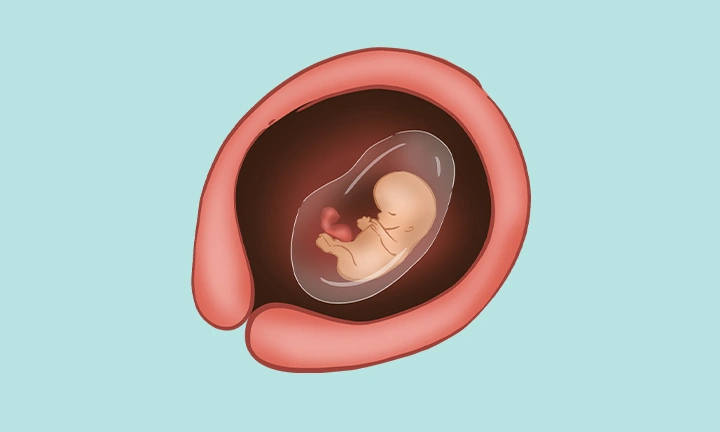

At week 10 of pregnancy, your baby is still tiny but growing rapidly. Floating safely in the warm amniotic fluid, your little one now measures about three centimeters in length. The body is becoming more proportionate— the head no longer looks oversized compared to the rest of the body.

Ankles and wrists have formed, and the tiny fingers and toes are now clearly visible. It’s hard to imagine, but your baby already looks more human than ever before.

During week 10, your baby’s internal organs are coming to life. A routine ultrasound may show that the yolk sac has disappeared and the umbilical cord, which connects the placenta to your baby, is now fully visible.